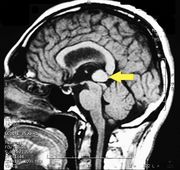

| 21:25, 26 February 2023 | Pineal cavernoma pre surgery 2.jpeg (file) |  |

161 KB | 1 | |

| 17:30, 26 February 2023 | Pineal cavernoma pre surgery 1.jpeg (file) |  |

128 KB | 1 | |

| 17:30, 26 February 2023 | Pineal cavernoma post surgery 1.jpeg (file) |  |

128 KB | 1 | |

| 17:30, 26 February 2023 | Pineal cavernoma pre surgery 2.jpg (file) |  |

853 KB | 1 | |

| 17:29, 26 February 2023 | Pienal cavernoma post surgery 2.jpeg (file) |  |

124 KB | 1 | |